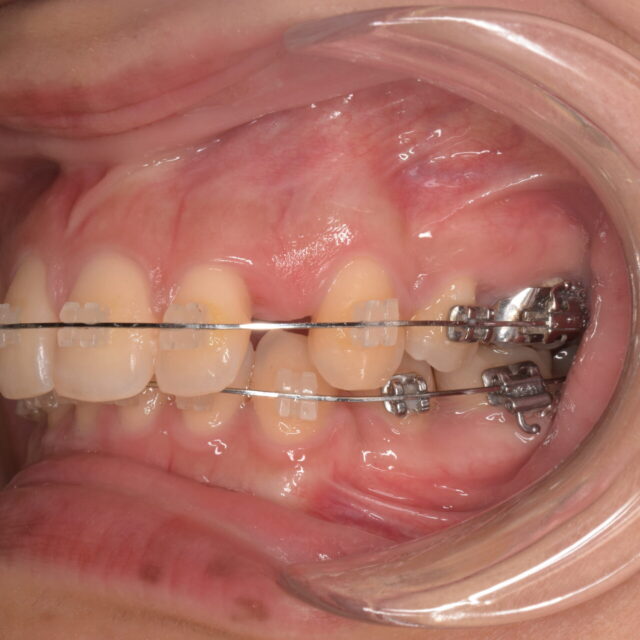

歯並びやかみ合わせの不調和は、見た目の問題だけでなく、咀嚼機能・発音・顎関節・全…

当院の矯正の紹介

当院では第三木曜日に矯正の先生に来ていただいてます。 三宅尚美先生です。 他院で…